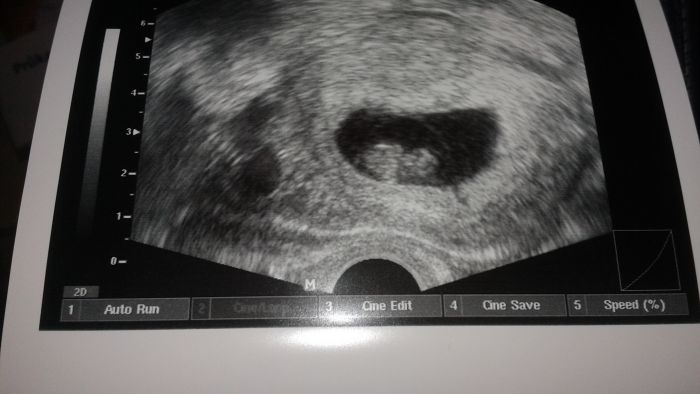

Tak konečně mám za sebou i já první prohlídku :) 8+2tt, termín porodu 12. 10. a mimi je teď 1,73cm velké :) Srdíčko má jako zvon a dostala jsem těhu průkazku :)

Musím pak poslat fotečku :) Pochlubit se z utz, ale taky s tím pupíčkem :) Tomu nebudete věřit :)

[710292] kráásná fotečka :) hlavně, ať je vše v pořádku :)

Je to legrace :) Myslela jsem, že jsou tam dvojčátka, když mám takový pupík, ale na utz se ukázalo jen jedno mimi ;)